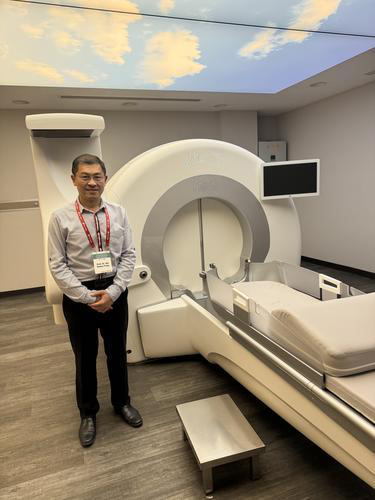

他感慨说道:“这些都是传统脑肿瘤手术的盲点,让人束手无策,常常让我陷入矛盾,感觉到深沉的无力感。”为了弥补外科手术的不足,他在今年7月前往土耳其伊斯坦堡科奇大学(KOC University)学习伽玛刀(Gamma knife),让手术刀和伽玛刀相辅相承,提高治疗效果。

全马仅4院提供治疗

虽然伽玛刀面市超过半世纪,但因为仪器本身非常昂贵,在大马仍不普遍,自2014年由一家私立医院率先引进后,目前国内只有4家医院提供伽玛刀治疗,所以民众对它了解不多。